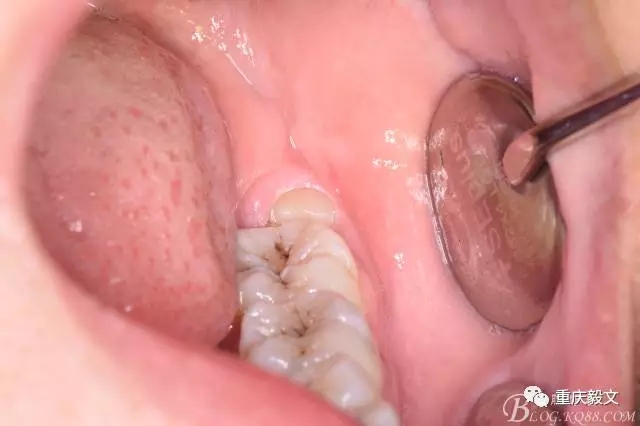

患者、李xx、女、20歲,主訴:左側(cè)下后牙牙齦不適數(shù)天。專(zhuān)科檢查:38水平位、牙冠萌出黃豆大小,頰側(cè)牙齦未見(jiàn)明顯紅腫,全景片檢查:38水平位、雙根、分叉大,37遠(yuǎn)中頸部未見(jiàn)齲壞。診斷:38中位水平阻生 治療計(jì)劃:微創(chuàng)拔除38。術(shù)前與患者充分溝通,告訴患者采用無(wú)痛sta阻滯麻醉加不切開(kāi)翻瓣拔除。患者同意手術(shù)方案,簽知情同意書(shū)。

圖2.口內(nèi)可見(jiàn)黃豆大小大遠(yuǎn)中面暴露,擬采用潛掘法分牙,分別取出牙冠、牙根,達(dá)到真正的微創(chuàng)拔牙